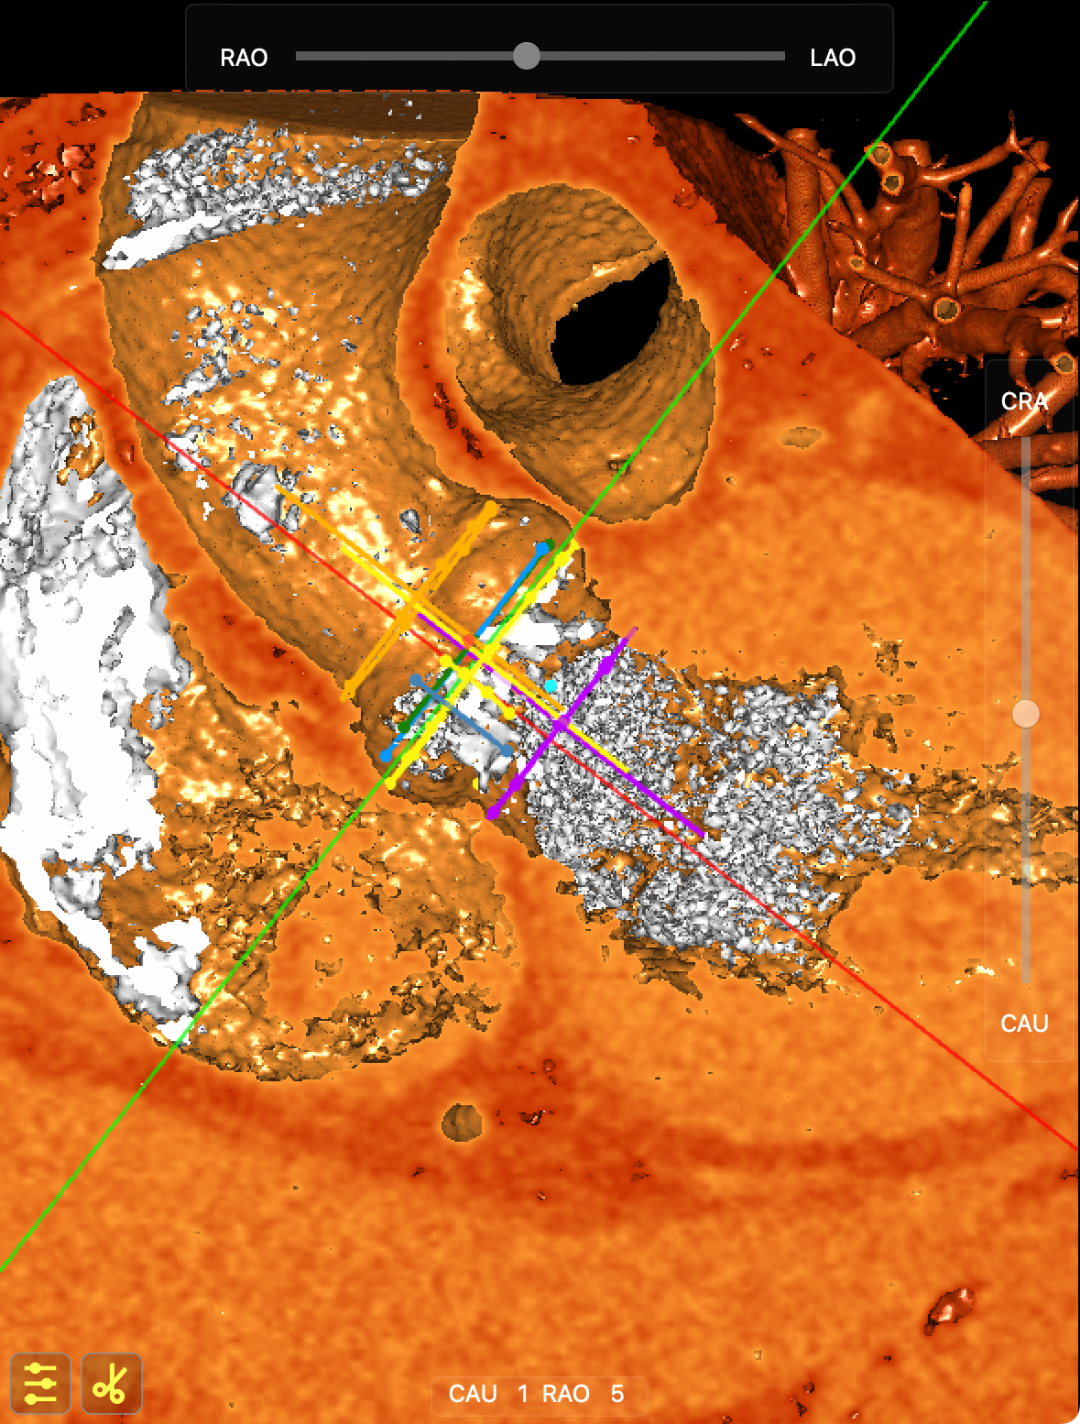

CT影像

该患者术前超声及CT提示主动脉瓣type0型二叶瓣中重度钙化,其解剖的特殊性对本次手术造成一定挑战,术前王焱教授团队对此进行了详细的术前规划,对可能存在的风险也进行了全方面评估,最终选择了适合患者的TruBeta®AV23经导管主动脉瓣瓣膜。

CT影像

手术策略

该例患者超声提示主动脉瓣三叶瓣钙化重度狭窄、中度反流,合并基础疾病多,且前不久因急性非ST段抬高型心肌梗死于LAD植入支架,身体状况欠佳,属于外科高危患者。在血管方面,患者存在主动脉弓部动脉瘤,胸、腹主动脉及其分支粥样硬化,在进行手术是需要注意保护血管,避免引发血管相关并发症。经术前CT评估,团队最终选择TruBeta®AV26规格经导管主动脉瓣瓣膜。